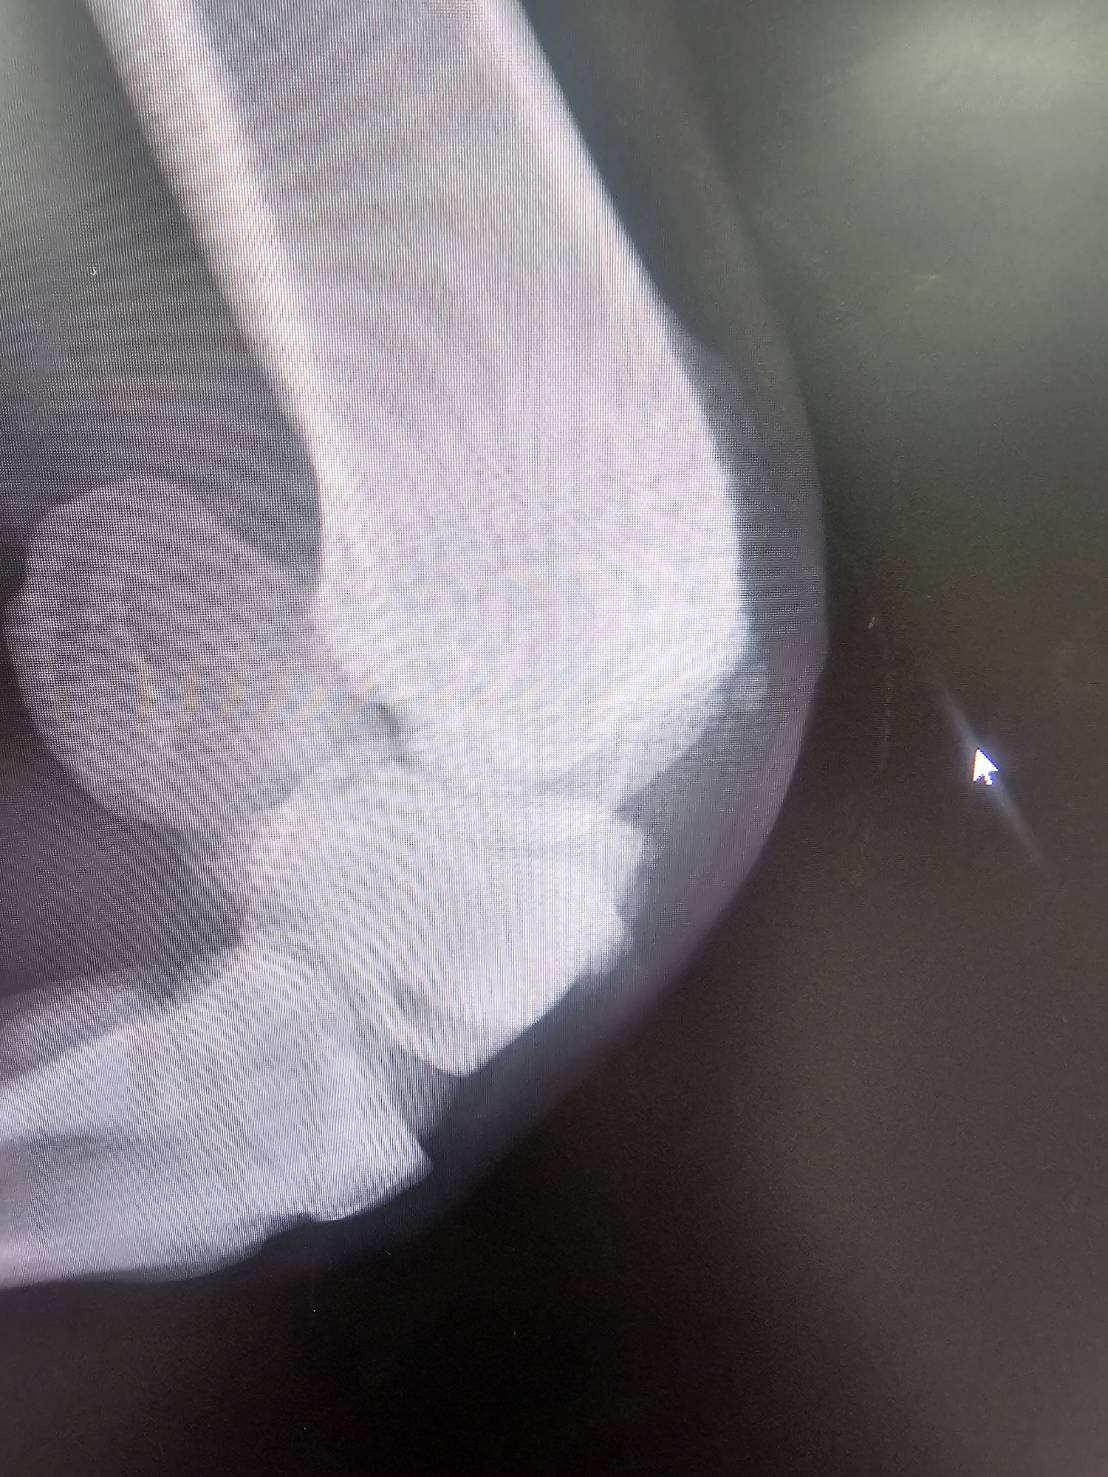

本馬は、美浦・中川公成厩舎から2024年10月20日の京都ダート1200mで馬体重500㎏でデビュー。16頭立ての14番枠からスタートを決めて4~5番手を追走すると、直線でメンバー3位タイの上がりを使い、逃げた勝ち馬から2秒1差、2着には0秒3差の3着に入ります。初戦からまずまずの手応えをつかんで迎えた中2週の東京ダート1400mでしたが、15頭立ての5番手から伸びを欠いて3秒0差の10着。レース後に右前肢の橈骨遠位端骨折発症が判明し(下記に詳細)、長期休養を余儀なくされます。

再転入初戦となった前走でしたが、右前肢の橈骨遠位端骨折を再発してしまいました。タイムオーバーの適用は除外となり、見舞金9号(競走中6カ月)が適用され、このタイミングでオークション出品となります。

※2026年2月21日の競走中、右橈骨遠位端骨折を発症。事故見舞金9号(競走中の事故により事故発生の日から6ヵ月以上出走できなくなった場合)の適用を受けています。なお、「タイムオーバーによる出走制限」の適用を除外されています。

※2024年11月10日の競走で、右橈骨遠位端骨折を発症。事故見舞金9号(競走中の事故により事故発生の日から6ヵ月以上出走できなくなった場合)を受給しています。